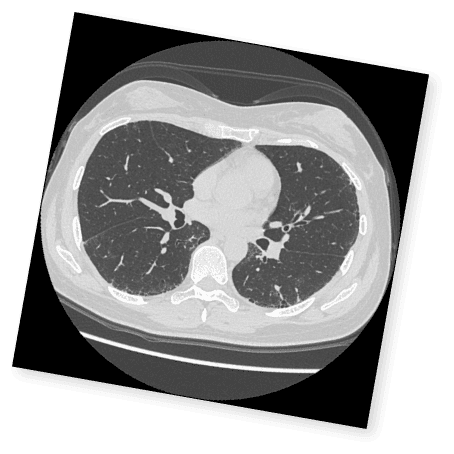

クイズで学ぶILDとILD-PH診断のポイント

実症例をもとに、画像や検査データから

間質性肺疾患および間質性肺疾患に伴う肺高血圧症の診断ポイントをクイズ形式で確認。

実践に即した診断力を養います。